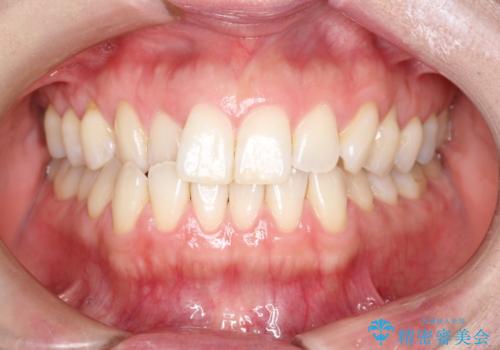

前歯の反対咬合をワイヤー矯正で改善して噛みやすく